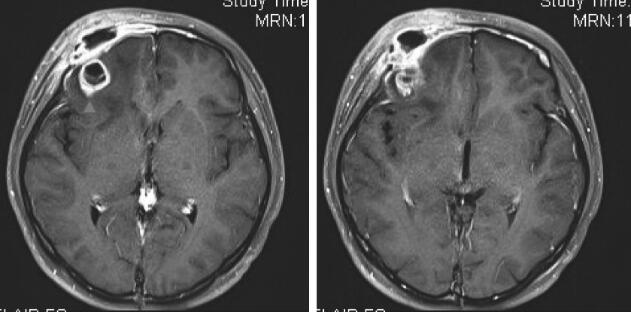

入院后2018年2月8日起予以头孢曲松2.0 g静脉滴注每12小时一次+甲硝唑0.5g静脉滴注每12小时一次治疗。同时联系相关科室取病理明确诊断。2018年2月9日眼科会诊指出:患者眼部大部分病灶在球后,不易活检,眼球前部病灶存在穿刺后伤口不易愈合风险,建议行脑穿刺活检。2018年2月8日及2018年2月11日先后两次出现发热,并感头痛,加用20%甘露醇125ml静脉滴注每12小时一次降颅压治疗,头痛缓解。2018年2月13日转神经外科行全麻下病变组织活检术,术中取右侧眉弓切口进入,切开肌肉后见病灶,灰红色,疏松,血供一般,质地软,病灶向深部侵犯骨质,取部分病变组织送冷冻,提示(眶上皮下)大量以中性粒细胞为主的炎性细胞浸润,伴类上皮反应,及朗格汉斯样多核巨细胞反应。再取部分病变组织送病理,培养及二代测序等。2018年2月14日转回抗生素研究所病房,再次出现发热、头痛,考虑手术后发热,需兼顾院内感染相关细菌;2018年2月16日调整抗感染方案:停用上述抗生素,换用哌拉西林/他唑巴坦4.5g每8小时一次,并将20%甘露醇125ml加量至每8小时一次降颅压治疗,患者体温逐渐下降;2018年2月20日体温平,头痛逐渐缓解,右侧眼睑皮肤红肿逐渐改善,略能睁眼,病情好转。期间血、脑脊液、手术活检组织培养均回报阴性,术中标本病原学二代测序阴性。术后2018年2月26日复查MRI(图3):右侧眶上外侧壁及周围软组织水肿略有吸收,右额异常强化灶略有增大。2018年2月26日手术病理结果:(右侧眶上皮下)朗格汉斯组织细胞增生症。故2018年2月26日起停抗感染治疗。

图3 术后2周复查MRI

右侧眶上外侧壁及周围软组织水肿略有吸收,右额异常强化灶略有增大